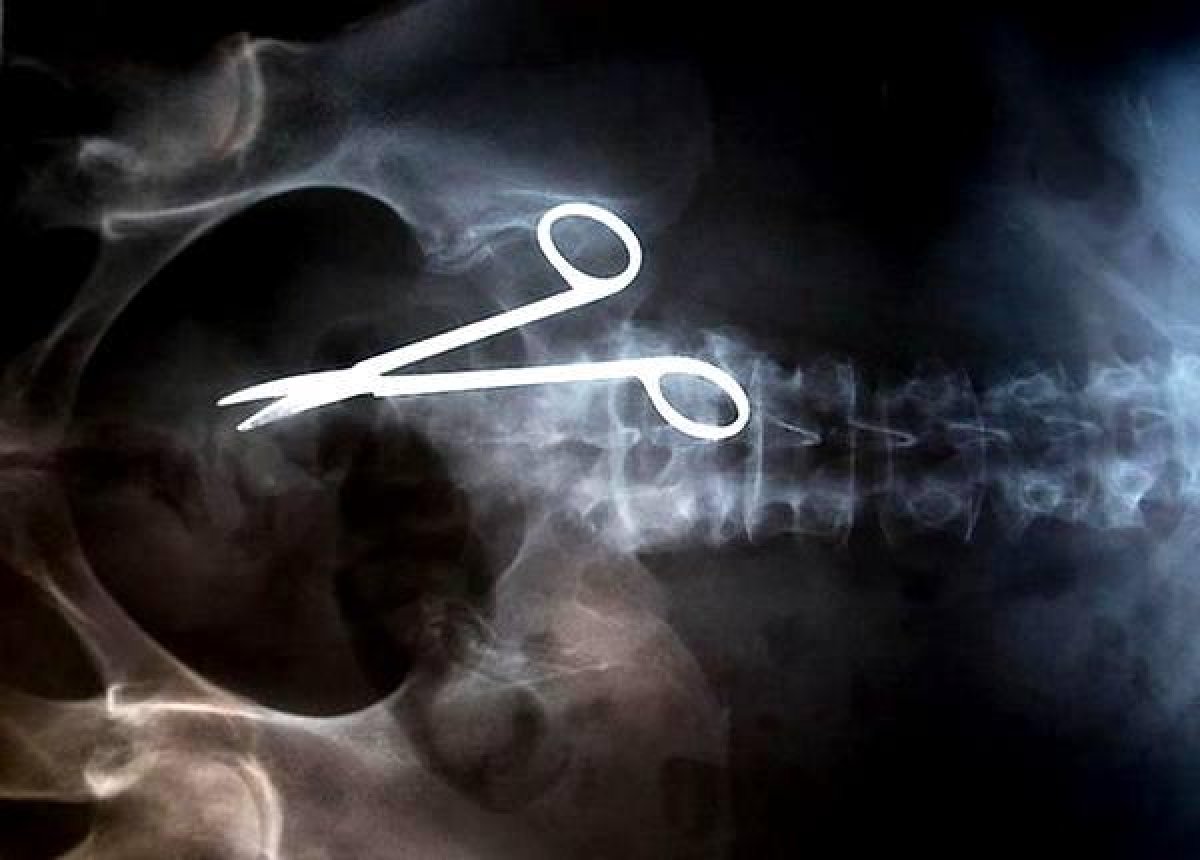

Иллюстративное фото

По словам жителя Отарского района, его жена и ребёнок стали инвалидами после неудачных родов, передаёт Astana TV.